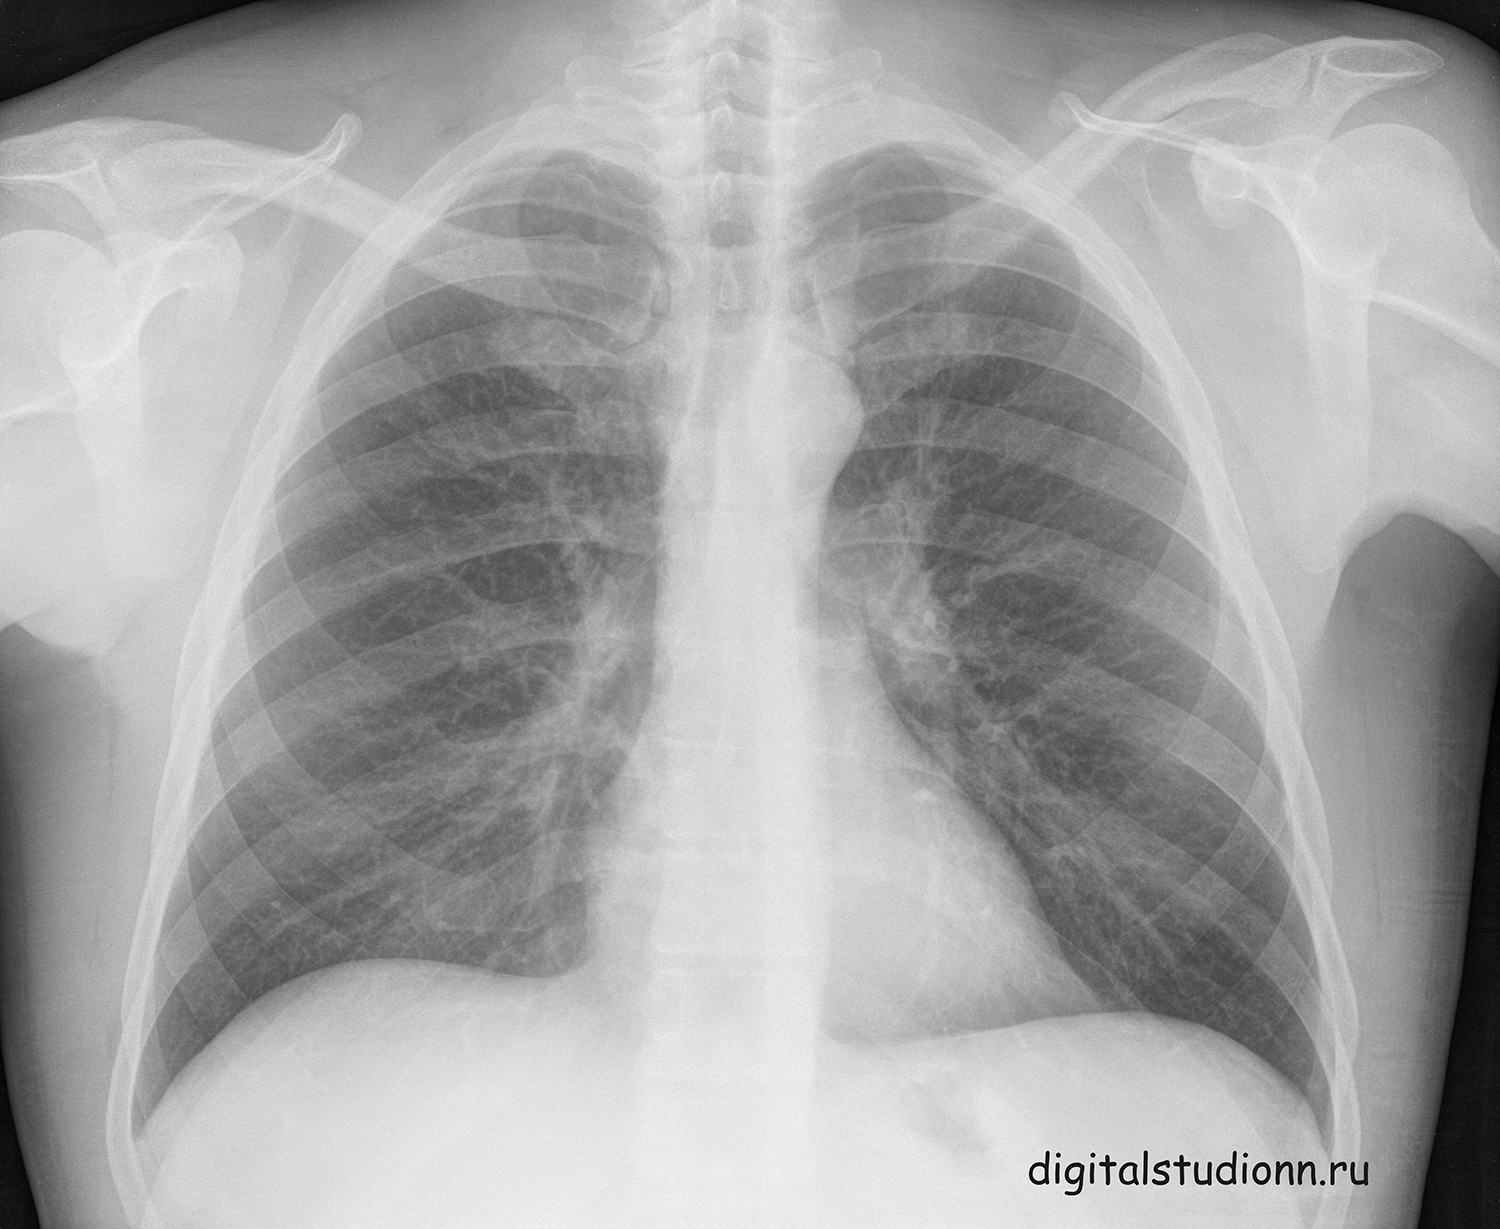

Что такое малоконтрастная рентгенограмма органов грудной клетки